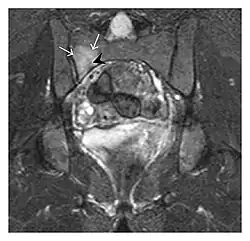

Proximal femoral fractures usually occur in osteoporotic patients, and their signs include subtle neck angulation, trabecular angulation, and subcapital impaction line. A frog-leg lateral view may be helpful if the greater trochanter is short enough. However, positioning can be difficult because of hip pain. In patients with strong suspicion of proximal femoral fracture and negative radiographs, MRI limited to coronal T1 W images and scintigraphy can be highly valuable (Figures 13 and 14). Such an option, with limited examination time, is cost-effective and allows reliable exclusion or confirmation of the diagnosis, preventing an unnecessary stay at the hospital or delayed treatment. Moreover, MRI helps to detect soft tissue abnormalities which are more frequently seen in femoral, acetabular, and pubic injuries than sacral lesions. Concomitant fractures are also frequently seen in typical pelvic sites.[1]

Figure 13: Partial osseous avulsion of the gluteal muscles at the greater trochanter in a 59-year-old man who presented with the right hip pain without a history of trauma. Lauenstein view and anteroposterior and radiographs (not shown) did not show an obvious fracture line or disruption of bony contours in the acetabulum or the right femoral neck. (a) Coronal T1-weighted MRI displays an incomplete fracture line extending partially from the greater trochanter (arrow). (b) Coronal short tau inversion recovery MRI shows heterogeneous hyperintensity in the same region (arrow) as well as hyperintensity within the gluteus medius and minimus muscles (arrowheads) consistent with tissue edema and hematoma.[1]